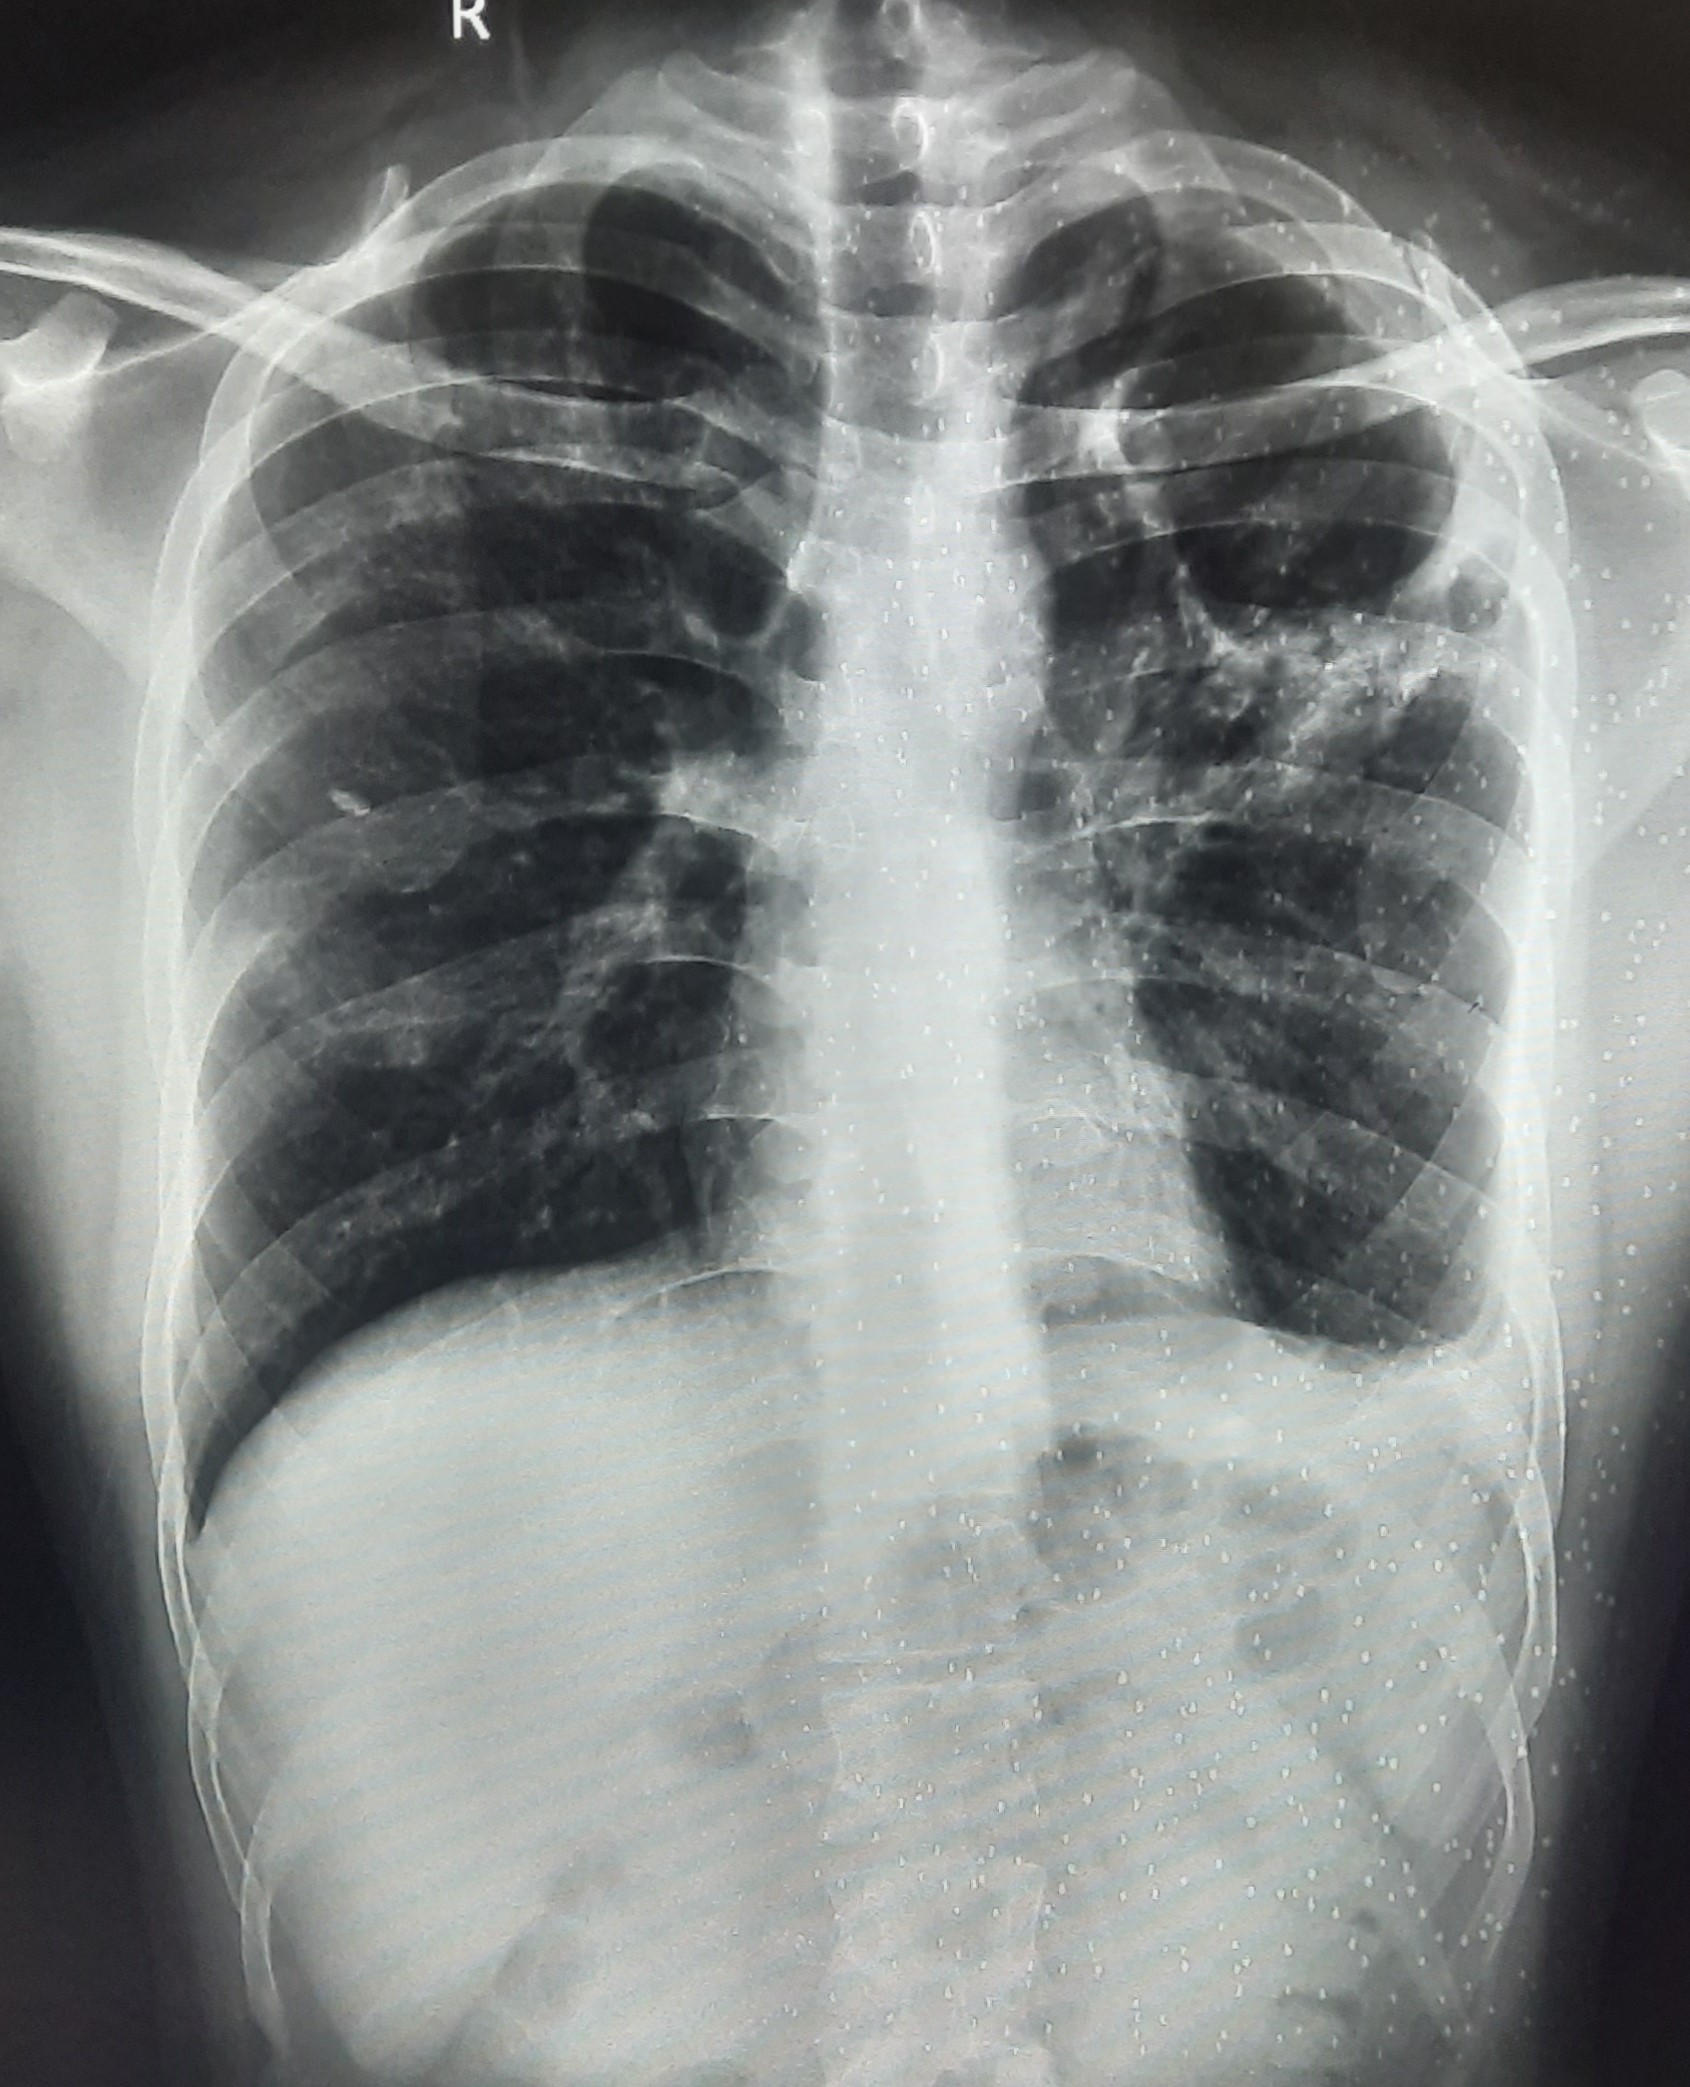

| 283 | IGGMC, Nagpur, Nagpur | P2 | 29-4189 Follow-up of 29-3923 |

Monali Pralhad Milmile | Consent taken on Paper | 46 Yrs. |

Provisional Diag : PTB Follow-up

Final Diag : Pleural Effusion |

TB Case (Confirmed) | Right Sided Upper Zone Fibrotic Lesion, Tracheal Pull Left side, Right sided & Left Sided Pleural Thickening Present, Right sided & Left Sided CP Angle Blunting Present, | Abnormality visible on x-ray |